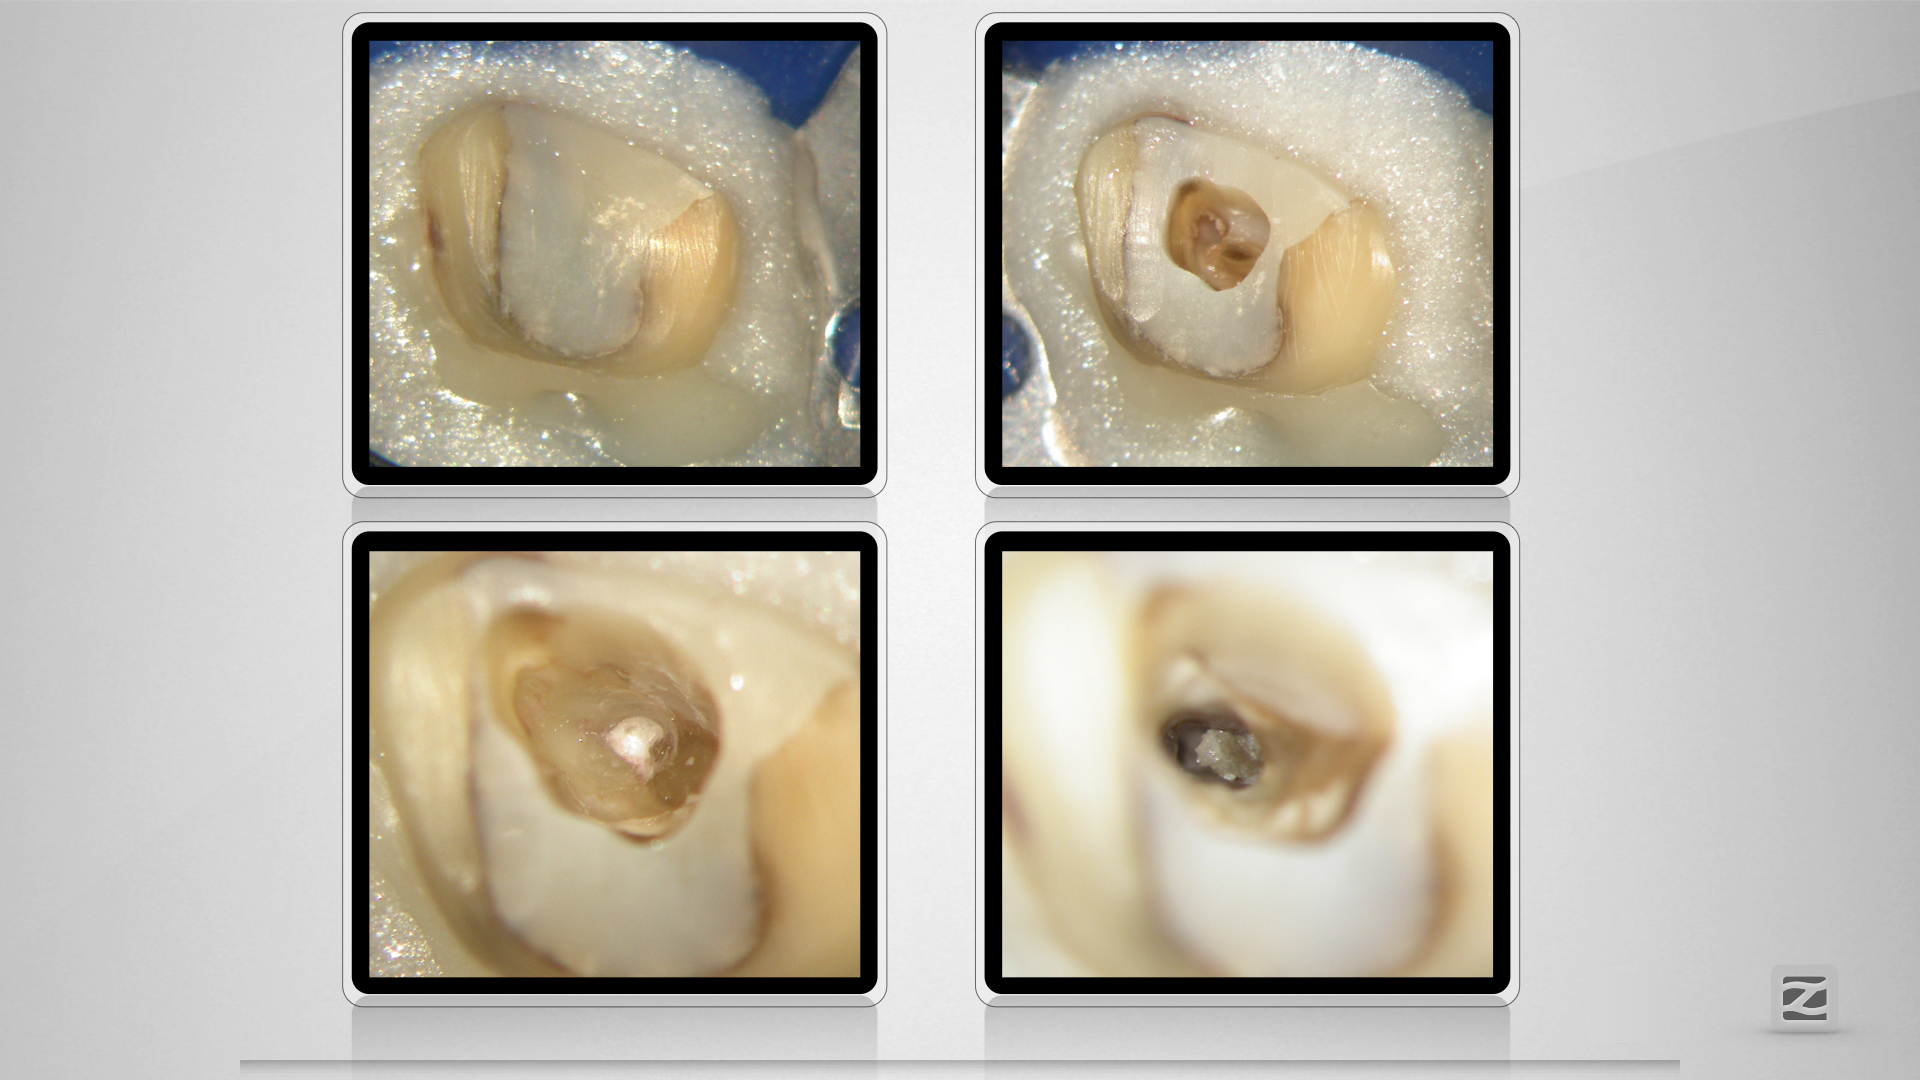

Großer Dentikel, tiefer Split.